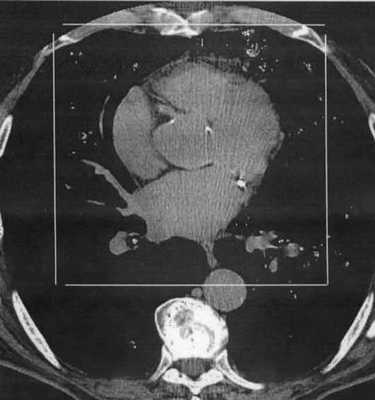

Компьютерную томографию производят при горизонтальном положении пациента. Основной срез сканирования выбирают таким образом, чтобы его плоскость проходила через центр митрального клапана и верхушку сердца. На томограмме этого слоя вырисовываются оба предсердия, оба желудочка, межпредсердная и межжелудочковая перегородки. На этом же срезе дифференцируются венечная борозда, место прикрепления сосочковой мышцы и нисходящая аорта. Последующие срезы выделяют как в краниальном, так и в каудальном направлении. Включение томографа синхронизировано с записью ЭКГ. Для того чтобы получить четкое изображение полостей сердца, томограммы выполняют после быстрого автоматического введения контрастного вещества. На полученных томограммах выбирают два изображения, сделанных в конечные фазы сокращения сердца - систолическую и диастолическую. Сопоставив их на экране дисплея, можно рассчитать регионарную сократительную функцию миокарда.

Рентгеновская компьютерная томограмма органов грудной клетки. Визуализируется кальциноз правой коронарной артерии (стрелка).

При КТ с болюсным контрастированием дифференцируются полости сердца, стенки желудочков, межжелудочковая перегородка, папиллярные мышцы, коронарный синус, листки клапанов. Этим методом распознаются морфологические изменения: аневризмы сердца, тромбы в его полостях, пара- и интракардиальные опухоли (визуализируются образования размером не меньше 1 см), аномалии развития крупных сосудов и аневризмы аорты.